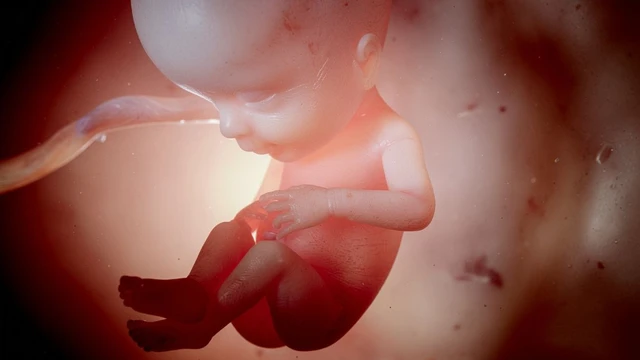

Bầu ho nhiều có ảnh hưởng đến thai nhi không? Đây là thắc mắc phổ biến của nhiều mẹ bầu khi gặp tình trạng ho kéo dài trong thai kỳ. Việc hiểu rõ nguyên nhân và mức độ ảnh hưởng của tình trạng ho là điều cần thiết để mẹ bầu có cách xử lý phù hợp, đảm bảo an toàn cho cả mẹ và thai nhi.